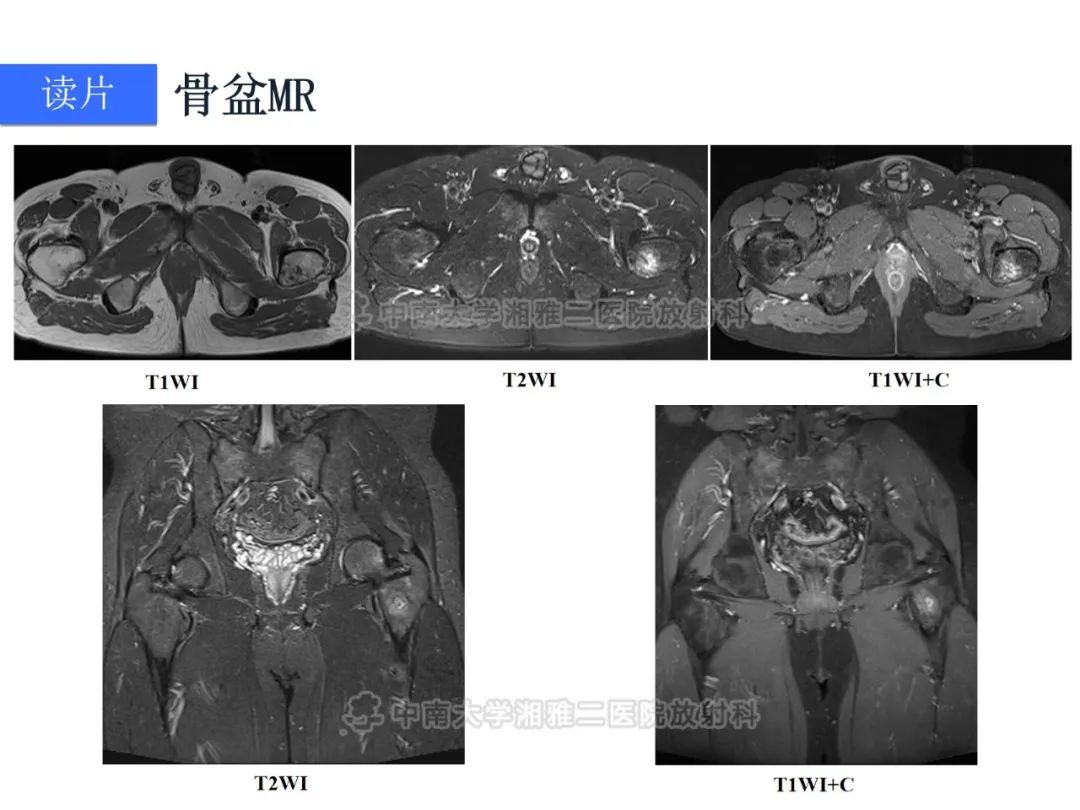

【病例】磷酸盐尿性间叶性肿瘤1例影像学诊断思路-4